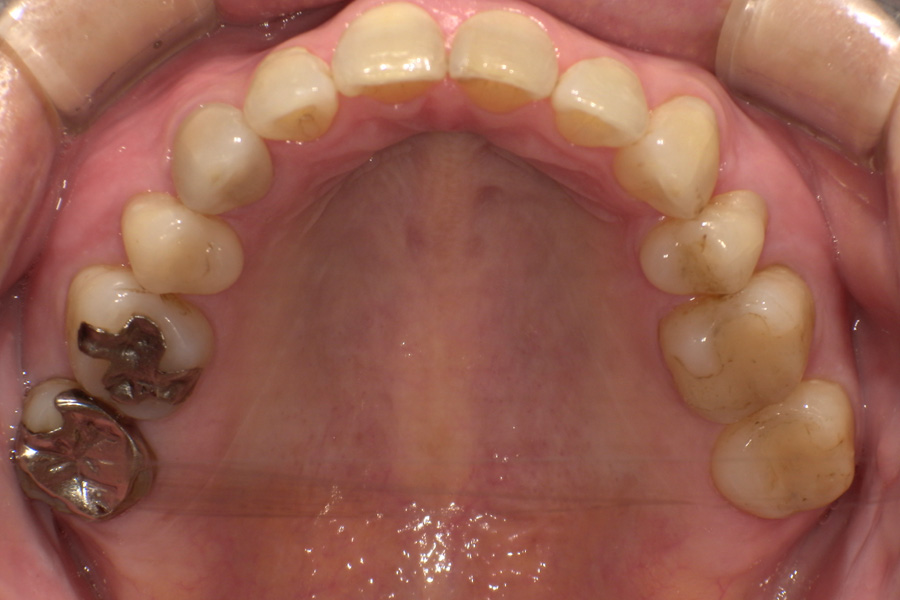

虫歯があるから削ったり悪くなったから抜くのではなく、まずは虫歯と歯周病が起きないようにより良い環境づくりをすること、そうすることによって歯を長く維持することが可能となります。

そのためには、健康状態に関する情報と生活習慣などの状況を把握したうえで、お口の中のリスク評価をおこないます。

その結果をもとに、お一人お一人にあった治療計画をご提案させていただきます。